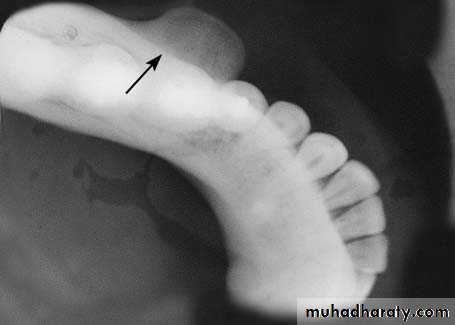

Torus Mandibularis

Torus mandibularis is an exostosis of unknown etiology.

It is localized in the lingual aspect of the body of the mandible, either on one side or more commonly on both sides (canine & premolar region).

Clinically, it is an asymptomatic bony protuberance covered by normal mucosa. Radiographically, it presents as a circumscribed radiopacity in the area of localization.

Torus mandibularis is completely innocent in nature and does not require any therapy whatsoever, except in cases where complete dentures are to be constructed.